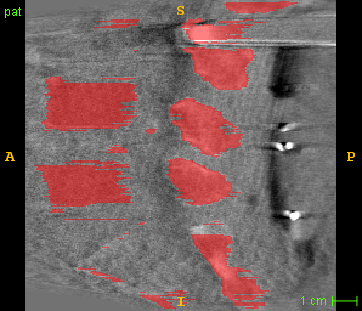

Disentanglement and explicit shape constraints. As shown in Fig. 4, we can see streak metal artifacts nearly everywhere in . M1 can roughly disentangle artifacts and anatomical information but strong vertical artifacts and strange air area appear in (see red arrows of M1 in Fig. 4). For the anatomical structure, M1 learns to segment vertebrae with fully supervised and applied on various CT images, but fails to suppress the false bony structure in and as may misclassify some metal artifacts as bone.

Implicit shape constraints. With , all segmentations are improved with higher Dices and smaller ASDs, see Table 1. As shown in Fig. 4, , and become similar but the high density bone is not correctly segmented in as it maybe treated as metal artifacts. Comparing between M2 and M1, the abnormal air region disappears but metal artifact reduction performance is still not satisfactory.

Anatomy-aware generation. With AADE layer in M3, , and are substantially improved as shown in Table 1. Note, is used as attention map, so we do not expect it to be identical to . In , metal artifacts are further suppressed comparing with M2. Thus, AADE is critical to our anatomy-aware artifact disentanglement framework. With the special structure, can be punished in the image translation and reconstruction processes and the other encoders and generators receive more guidance. However, as shown by blue arrows in Fig. 4, we observe a shadow of vertebra edge of appears in of M3 and the vertebra boundaries get smoothed out in . It may be because sharp edges are encoded as metal artifacts and forced to be added to by artifact consistency loss .

Removal of . To mitigate vertebrae shadows, we remove . The segmentation performance of most images in M4 gets improved because of better synthetic images. Overall, in M4 yields the best segmentation performance for CBCT images with an average Dice of 0.847 and an average ASD of 1.54 mm. For the synthetic images, M4 generates with the best quality and least metal artifacts among all the models. M4 also outputs without vertebra shadows. The results indicate our shape-aware network could preserve anatomical details and transfer the metal artifacts precisely without .